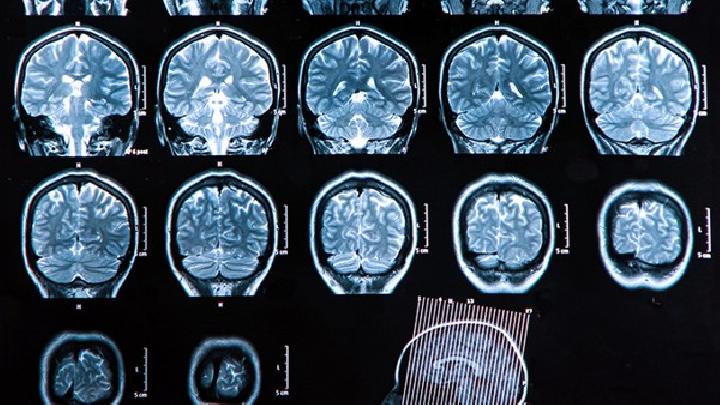

腦萎縮可能由阿爾茨海默病、腦血管疾病、亨廷頓舞蹈病、多發(fā)性硬化等疾病引起,早期表現(xiàn)為記憶力減退,進(jìn)展期出現(xiàn)認(rèn)知障...